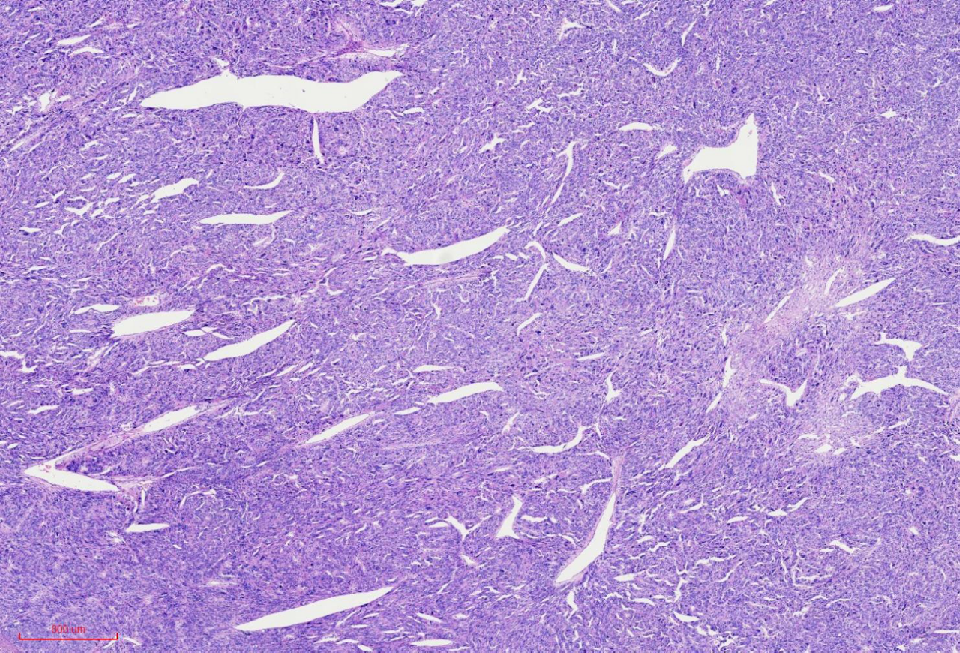

组织学改变

肿瘤与周围境界清楚

肿瘤细胞丰富

瘤细胞排列呈血管外皮瘤样

瘤细胞疏密相间

肿瘤境界清楚

细胞丰富

鹿角样/血管外皮瘤样血管

肺水肿样水肿/疏密相间